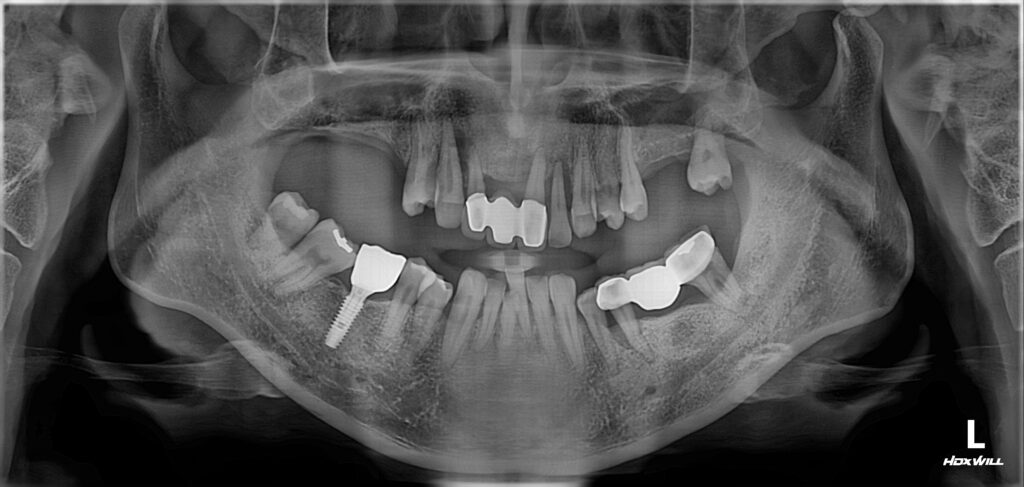

40대 남성분이 위와 같은 상태로 치과에 내원하셨습니다.

문제점 파악

1. 어금니와 앞니 쪽 잇몸 염증이 심해서 치아가 많이 흔들리고 있었습니다. (노란색 화살 표시)

​해당치아들은 발치를 해야 할 만큼 상태가 많이 안 좋았네요.

​어금니가 먼저 무너지고 어금니가 지지를 해주지 못하니까 앞니 쪽에 많은 힘이 가해져서 결국 앞니가 버티지 못하고 흔들리게 된 것으로 추측이 됩니다.

​​어금니가 건재해야 앞니도 건강합니다.

​상악 어금니의 경우 임플란트 심기에 뼈가 부족해서(흰색 실선) 상악동 거상술을 통해 뼈를 만들어줘야 했습니다. (초록색 실선)